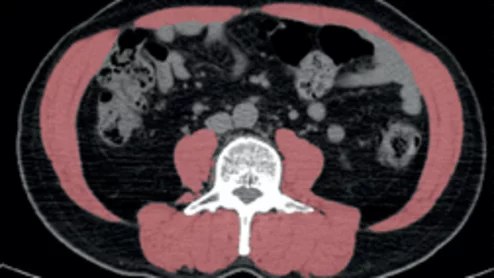

Nuclear cardiology is entering a new era—one that goes well beyond the traditional focus on myocardial perfusion imaging. According to Marcelo Di Carli, MD, editor-in-chief of the Journal of Nuclear Cardiology and chief of the Division of Nuclear Medicine at Brigham and Women’s Hospital, the field is rapidly expanding into diagnosing and monitoring complex cardiac diseases such as amyloidosis, sarcoidosis, myocarditis, and cardiac infections.

Beyond amyloidosis, nuclear cardiology is also increasingly used to image inflammation and infection in the myocardium, especially in diseases such as cardiac sarcoidosis and myocarditis.

PET has already gained significant momentum in recent years. Now, researchers are pointing to another possible use for the popular imaging modality: assessing carotid artery atherosclerosis.